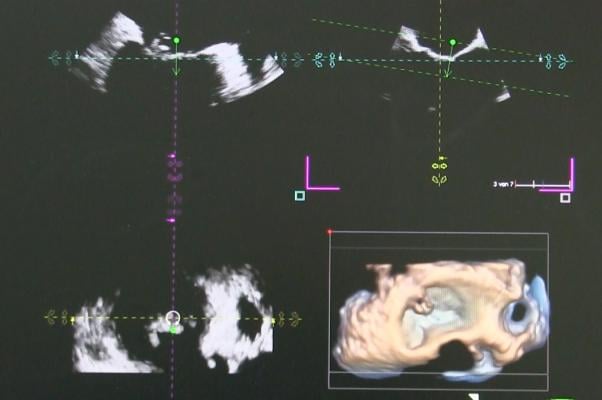

Echocardiography is the most widely used cardiac imaging modality but access to echo in point-of-care settings is often limited because it requires specialized skills to perform. Bay Labs has developed guidance software that uses artificial intelligence (AI) to aid in the acquisition of echocardiograms. The Bay Labs technology is designed to provide both non-specialist and specialist healthcare providers with real-time guidance to obtain 10 standard echocardiographic views, and designed to be integrated into an ultrasound machine. First-time data will be presented which compares the diagnostic quality of echocardiograms obtained by registered nurses (RNs) with limited training using Bay Labs technology, to the images obtained by a trained cardiac sonographer. Bay Labs guidance software is for investigational use only and not for sale.

“Evaluation of a Deep-Learning Model Designed to Aid Novice Scanners in Obtaining Diagnostic Quality Echocardiograms” will be presented by Akhil Narang, M.D., of Northwestern Memorial Hospital.